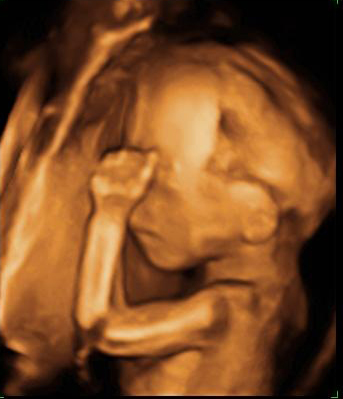

En esta imagen obtenida con una ecografía en 4D de un feto de 20 semanas de gestación se contempla cómo el bebé mueve sus brazos delante de su cara. Aún se encuentra muy delgado, ya que es a partir del tercer trimestre, sobre todo, cuando el feto empieza a acumular grasa bajo su piel.

Ecografía de bebé de 20 semanas de perfil

Podemos ver claramente los miembros superiores: el feto flexiona los brazos y los pasa por delante de la cara